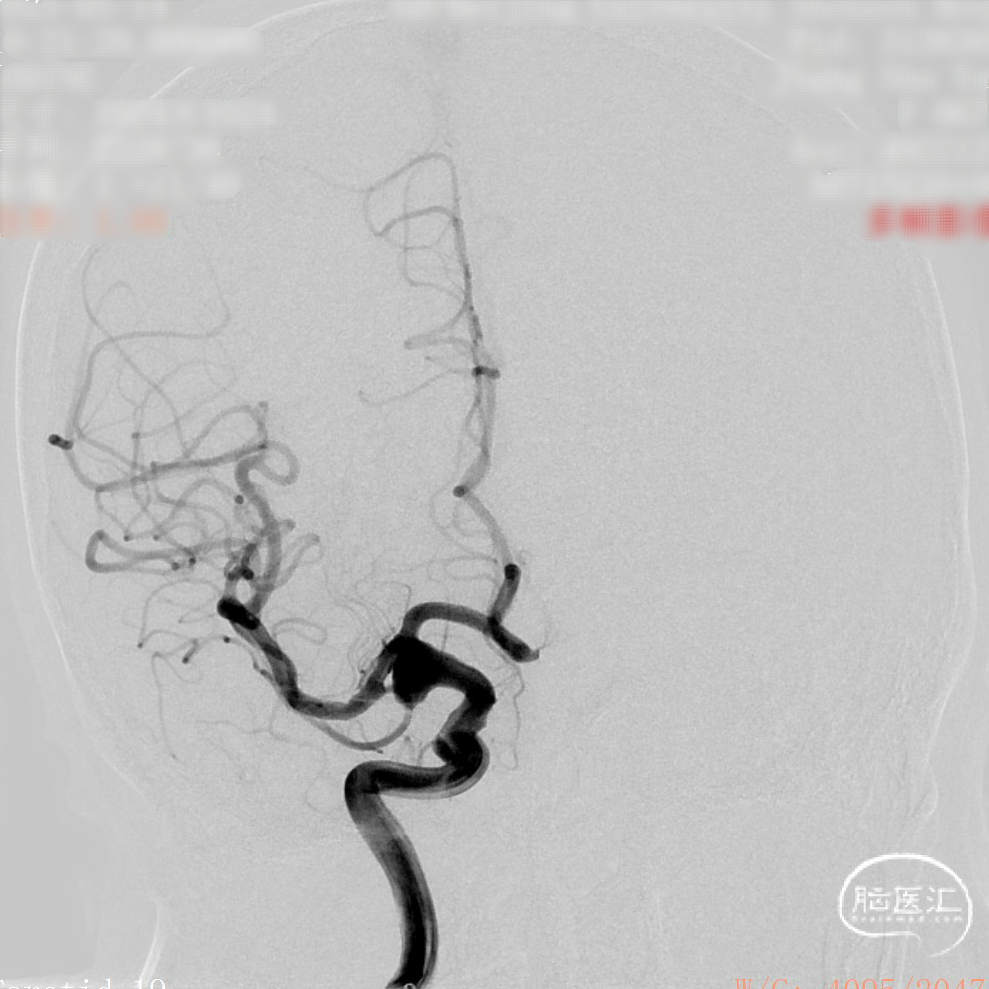

CTA:右侧颈内动脉C7段动脉瘤。

老年女性患者,检查发现右侧颈内动脉C7段大动脉瘤,动脉瘤直径大于10mm,形态不规则,宽颈,手术指征明确,既往高血压、肿瘤病史,首选微创介入手术,术中造影证实动脉瘤直径大于10mm,绝对宽颈,形态不规则,局部仔瘤改变,右侧脉络膜前动脉从瘤体发出;微创介入血流导向装置是较优选择。

DSA造影:

正侧位造影:支架放置后可见动脉瘤内造影剂明显滞留。